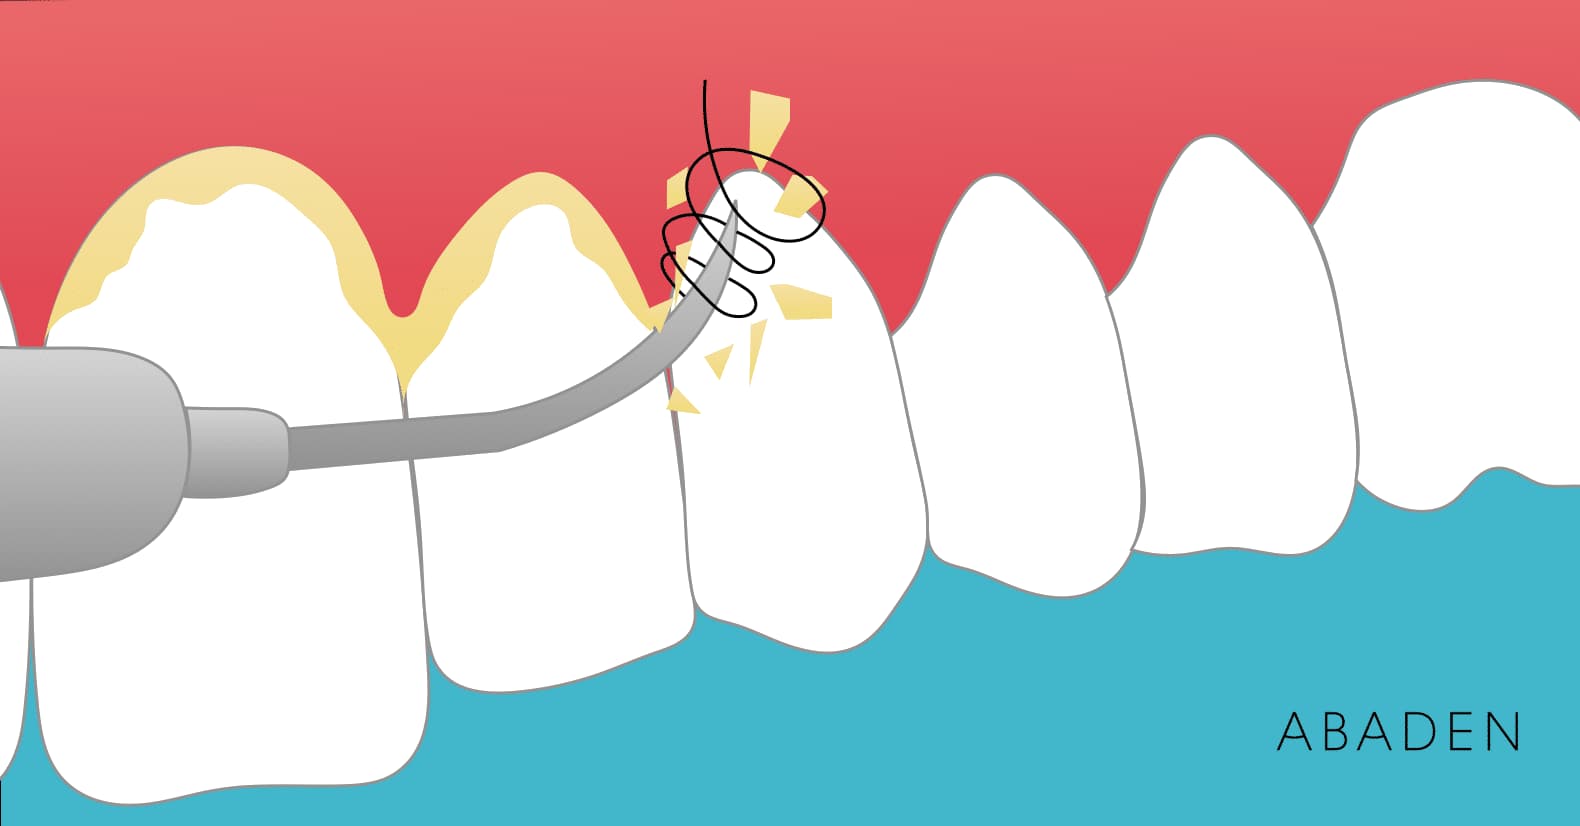

Ácido hialurónico en odontología

El ácido hialurónico se utiliza a en multitud de campos de la medicina, a pesar de que lo más probable es que lo que más no suene es su uso en el campo de la estética con el fin de rellenar y corregir arrugas aunque lo cierto es que el ácido hialurónico tiene infinidad de … Leer más